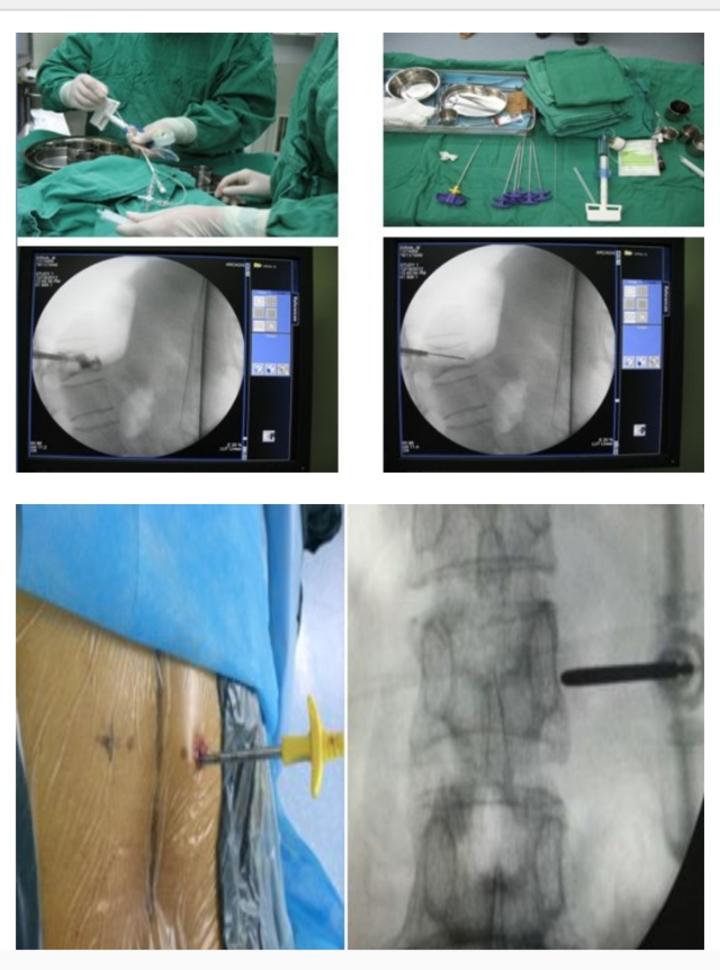

多节段胸腰椎骨折微创PKP手术

1440x1557 - 260KB - JPEG